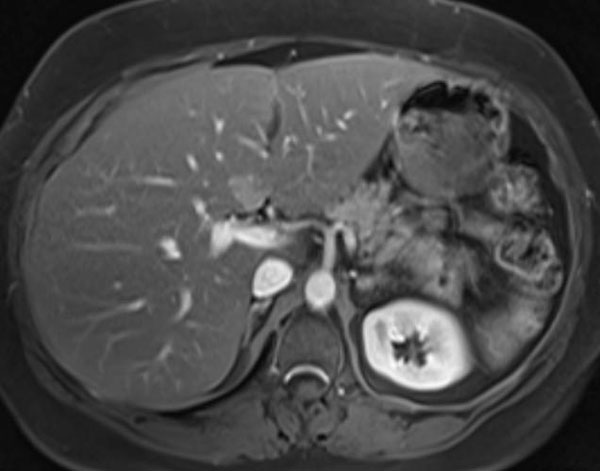

Методы динамического контрастирования печени на МРТ

Раздел: Снимки-подсказки